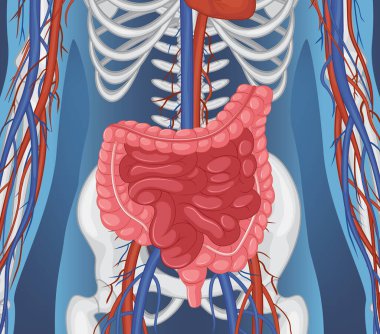

Sindirim Sistemi

MaviresimlemeİnsanKadınSağlıkkanİlaçAğızSolunumerkekkalpgövdeMidebiyolojiBilimSistemözetorgİskeletanatomiKas gücübeyinSistemlersindirimGerginakciğerlerkaraciğerBöbrekiskeletOrganlaranatomikBağırsaklarBağırsakKolondolaşımdalakBenzer İçerikler